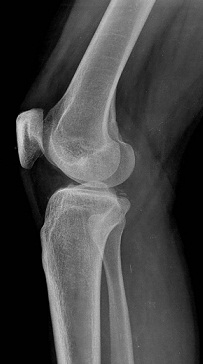

반월상 연골열상이란 반월상 연골판이 찢어지는 것을 말한다. 무리한 동작이나 급격한 방향전환 중 연골판이 찢어지는 경우가 많기 때문에 운동선수들에게 나타나는 부상의 다수를 차지하고 있다. 반월상 연골판이 무엇인지 간단히 설명하자면 허벅지 뼈(대퇴골)와 종아리 뼈(경골) 사이에 위치한 반달모양의 물렁뼈로서 완충역할을 할 뿐 아니라 관절연골에 영양분을 공급하는 중요한 역할을 담당하는 부분이다.

이러한 중요한 부분의 손상인 반월상 연골열상은 운동선수들에게는 치명타가 된다. 무릎을 구부렸다가 완전히 펴지 못하기 때문에 증상이 호전될 때까지는 제대로 운동을 할 수가 없는 것이 그 이유이다. 그렇기에 결코 간과할 수 없는 질환이라고 할 수 있다.